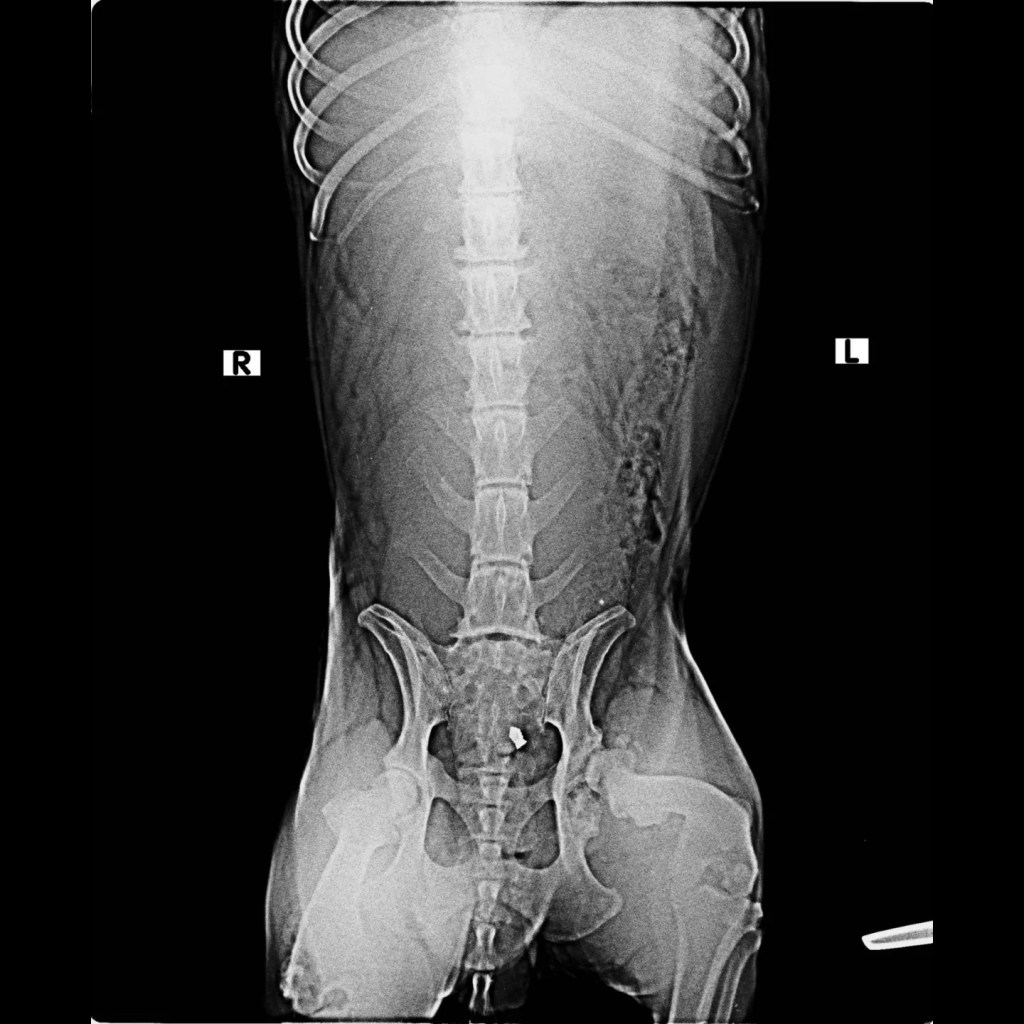

Sent her to the vet and got x-rays to reveal that she’s got a hook fracture on the spine. It will take about 10-15 days to heal and pain to subside. She won’t be able to get up till the pain subsides.